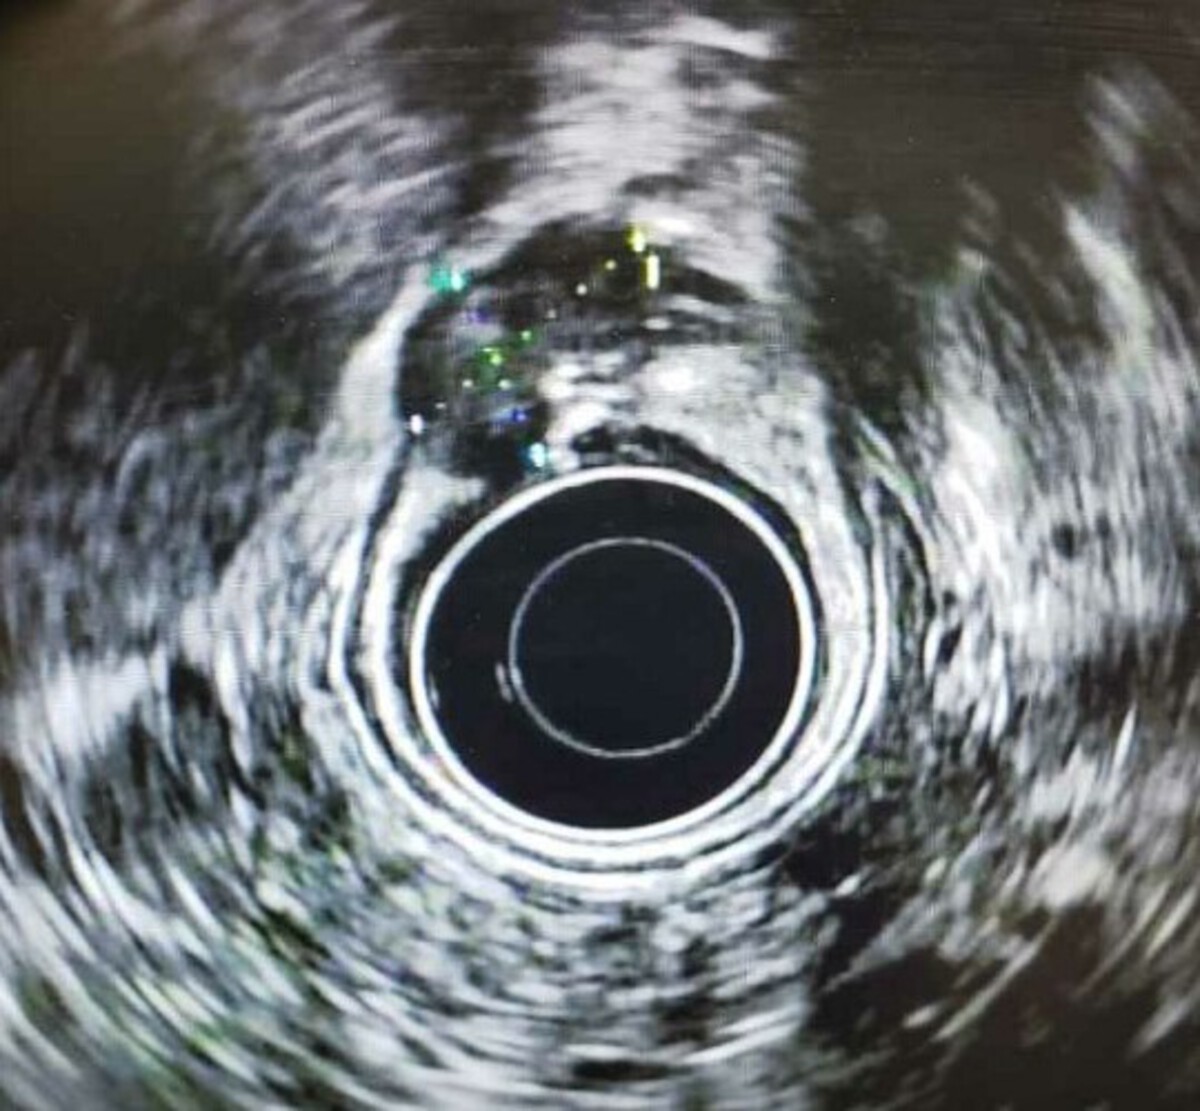

A 55-year-old man underwent upper endoscopy for abdominal pain and weight loss. He was found to have a 1.5-cm ulcerated mass in the antrum [figure A]. Biopsies confirmed a well-differentiated adenocarcinoma. Staging CT chest/abdomen/pelvis, EUS and a PET scan did not reveal positive nodes or metastatic disease. EUS of the gastric mass is shown [figure B]. What would be the best next step in the management of this patient?

The lesion shown is a T2N0M0 based on the invasion of muscularis propria on EUS and absence of nodes and metastatic disease. Endoscopic resection of any modality is restricted to less than 3 cm (ulcerated) or 2 cm (poorly differentiated – expanded Japanese indications) lesions that do not have lymphovascular or perineural invasion and do not have invasion more than 500 microns (0.5 mm) within the submucosa (sm1). The NCCN guidelines have more conservative limits on the size of lesions that can be resected endoscopically, all guidelines agree that for T2 lesions, consideration of perioperative chemotherapy and surgery are current standard of care and should be recommended for this patient.